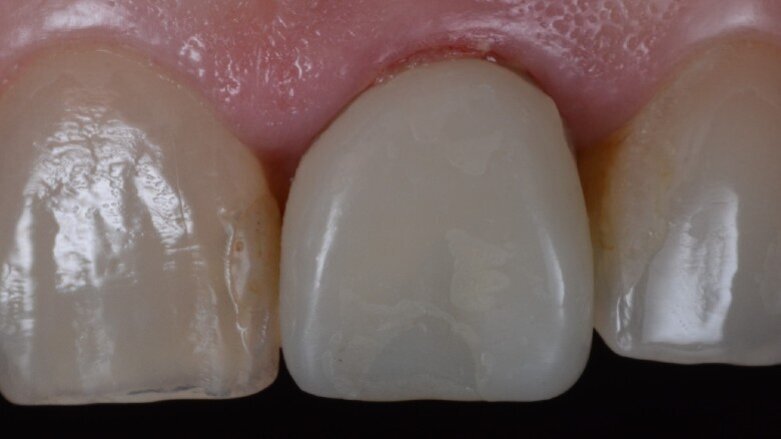

Un abutment provvisorio di Ø 4 mm con un’altezza gengivale di 2,5 mm è stato posizionato sull’impianto e non ha mostrato interferenze sulla cresta ossea, consentendo un adeguato profilo di emergenza (Fig. 19). Il guscio del dente, che è stato progettato e fresato in PMMA prima della procedura (Figg. 20, 21), è stato testato per assicurarsi che i contorni e le ali di ritenzione fossero adeguati e non causassero interferenze (Figg. 22, 23). Il lato palatale, comprendente una piccola porzione del bordo incisale, è stato aperto per consentire l’accesso al canale della vite (Figg. 24, 25). Le ali laterali del guscio del dente permettono alla corona provvisoria di rimanere immobile durante la procedura di prelievo, problema comune che i medici si trovano ad affrontare quando eseguono la tecnica pick-up immediata. Il guscio del dente è stato incollato al moncone provvisorio con composito flow fotopolimerizzabile ed è stato lasciato un sottile profilo di emergenza sulla porzione sottogengivale con lo stesso materiale (Fig. 26). A questo punto, le ali di ritenzione sono state rimosse. Senza compressione sui tessuti molli, la corona provvisoria è stata posizionata e il bordo incisale è stato ritoccato per garantire che il dente antagonista non lo toccasse nei movimenti di escursione. La corona provvisoria è stata cementata con un torque di 25 Ncm e il foro di accesso della vite è stato chiuso e lucidato correttamente (Fig. 27). Il paziente è stato visitato sette giorni dopo per il controllo radiografico postoperatorio e periapicale (Figg. 28, 29).

Fig. 27_Corona provvisoria posizionata e lucidata.

La protesi finale è stata progettata utilizzando Straumann CARES Visual con un workflow digitale. Durante la fase di progettazione è stato possibile vedere che il foro di accesso della vite sarebbe rimasto completamente sul lato palatale senza alcuna interferenza con l’estetica del restauro. Una corona monolitica in ceramica (Prettau Zirconia, Zirkonzahn) è stata fresata e cementata fuori dalla bocca su un’ampia base regolare Variobase (Straumann) con un’altezza gengivale di 1,5 mm, corrispondente al rimodellamento terapeutico dell’architettura ossea (Fig. 30). Dopo il controllo dell’occlusione, dei punti di contatto e dei movimenti di escursione, il restauro è stato inserito e avvitato con un torque di serraggio 25 Ncm (Figg. 31–33).

Fig. 30_Corona monolitica in ceramica cementata su abutment Variobase.

Fig. 32_Risultato finale da vicino.